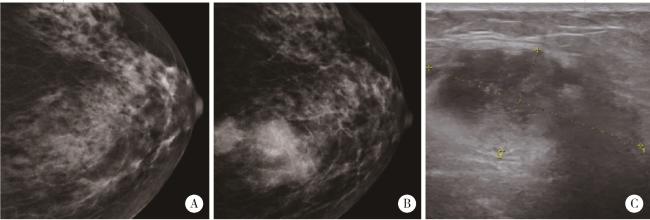

图2 左乳腺肿块钼靶X线检查Figure 2 Left breast mass examination A, mammogram (October 2021), multiple flaky or slightly high-density shadows are observed, with no apparent tumor identified; B, mammogram (October 2023), multiple circular and slightly high-density shadows are noted in the upper quadrant, approximately 8.5 cm from the nipple. The most extensive lesion measures approximately 3.5 cm×2.6 cm, with slightly blurred margins (Assessment: BI-RADS 4C); C, breast ultrasound (October 2023), a hypoechoic mass measuring 4.0 cm×1.9 cm is identified, exhibiting an irregular shape, indistinct margins, and no significant posterior acoustic changes (Assessment: BI-RADS 4B). |